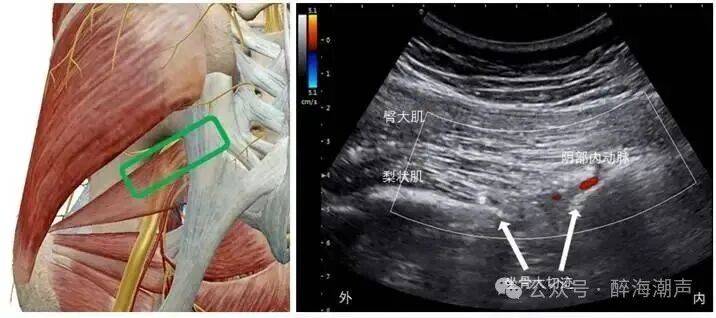

图源:醉海潮声

图示:超声引导梨状肌阻滞

图示:超声引导坐骨棘水平阴部神经阻滞

图示:超声引导Alcock管入口处闭孔内肌阻滞